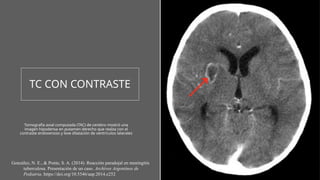

TC CON CONTRASTE

Tomografía axial computada (TAC) de cerebro mostró una

imagen hipodensa en putamen derecho que realza con el